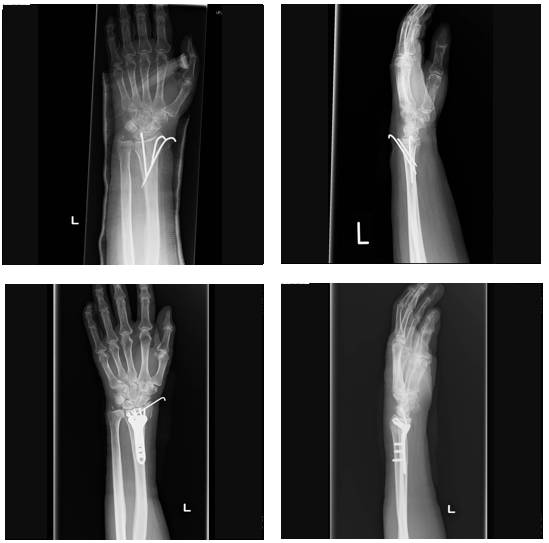

복합 골절이나 사선 골절, 분쇄 골절처럼 골절 양상이 복잡한 경우에는 완치 기간이 더 길어집니다. 이 경우 수술적 치료를 시행하고 금속 핀이나 금속판으로 고정하는 경우가 많으며, 수술 후에도 일정 기간 깁스나 보조기를 착용해야 합니다. 수술 후 뼈 유합까지는 최소 8~10주가 필요하고, 이후 재활 치료까지 포함하면 완전한 기능 회복에는 4~6개월 이상이 소요될 수 있습니다. 특히 손목을 많이 사용하는 직업군이나 스포츠 활동을 병행하는 경우에는 회복 기간을 더 길게 잡는 것이 안전합니다.

수술을 동반한 손목 골절의 경우 깁스 기간은 대체로 6~8주 이상으로 길어집니다. 금속 고정물이 삽입되었다고 해서 바로 깁스를 제거할 수 있는 것은 아니며, 내부 고정과 외부 고정이 병행되는 경우가 많습니다. 수술 직후에는 통깁스를 착용하고, 이후 회복 경과에 따라 보조기 형태로 전환하는 방식이 일반적입니다. 깁스를 제거하는 시점은 단순히 통증이 줄어들었다는 이유가 아니라, 영상 검사상 뼈 유합이 안정적으로 확인되는지를 기준으로 결정됩니다.